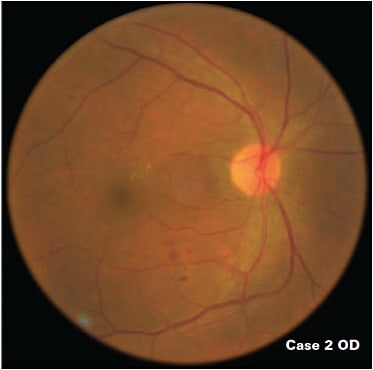

Although longer disease duration is an important predictor of diabetic retinopathy, about 30% of patients with type 2 diabetes have diabetic retinopathy at the time of diabetes diagnosis.12 Most of these patients likely had diabetes for several years before they were diagnosed. Case 2 is an example: a 48-year-old Hispanic male without a history of diabetes who has diabetic retinopathy.

Case 2: 48-year-old Hispanic male with moderate diabetic retinopathy at the time of diabetes diagnosis